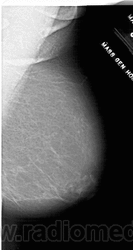

Жирная (не плотная) грудь

Умеренно плотная грудь

Плотная грудь

Маммограммы представляют собой изображения структур, проецируемых на плоскость: плотная грудная маммограмма, следовательно, состоит из многих других структур, которые необходимо проанализировать, чем более жирная, пустая грудь. По этой причине диагностировать рак молочной железы труднее для моложе, чем для пожилых женщин.

Нажмите на миниатюрные картинки, чтобы получить увеличенный размер.